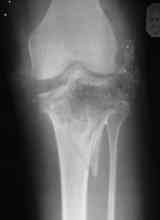

Уважаемые коллеги! На консультацию обратилась женщина, 23 года. В феврале огнестрельное ранение колена. Снимки первичные и майские в приложении. А также внешний вид раны. Укорочения конечности нет. Разгибание в коленном суставе отсутствует. Сгибание сохранено. Нестабильности нет.Дно раны - мертвая кость.

по снимкам у пациентки на данный момент сохраняется дефект наружного мыщелка б\б кости, который со временем приведет к вальгусной дефеормации голени и в настоящий момент практически отсутствует бугристость б\б кости, т.е. зона прикрепления собвственной связки, которую можно в принципе выкроить из средней порции сухожилия 4-хглавой со средней частью надколенника, но сначала необходимо запонить дефект костной ткани, либо путем свободной кости пластики, либо формированием отщепа б\б кости с микродистракцией в КДА Илизарова. т